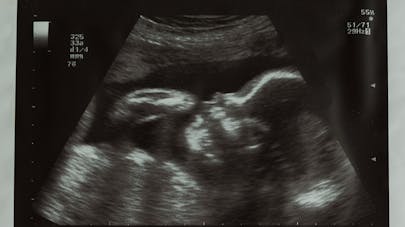

échographie a 6 semaines de grossesse Résolu /Fermé juste un renseignement, je voudrais savoir pour celle qui on aussi fait une échographie à 6 semaines ce que vous avez vu exactement, moi j'ai vu le petit bebe dans le sac et le tache blanche qui clignote qui est le coeur qui bat, le mec qui m'a fait l'échographie m'a dit que j'etais enceinte de 6 semaines car je ne savais pas de quand remontait la grossesse mais il ma dit qu'il voulais me revoir a 8 semaines car le coeur du bebeUne nouvelle semaine démarre En cette 6ème semaine de grossesse, découvrez l'évolution de votre bébé et de votre corps !En milieu de semaine, votre embryon fera ses premiers mouvements

La 8ème semaine de grossesse (10 SA) correspond à la dernière phase embryonnaire L'organogenèse se termine et l'embryon devient fœtusIl mesure alors 3 cm et pèse 2 à 3 gr Tout, ou19 semaines de grossesse Croissance et développement de bébé Votre bébé pèse environ 300 grammes et mesure plus ou moins 21 centimètres À 19 semaines de grossesse, les oreilles et les yeux du bébé sont encore fermés mais ils approchent de leur emplacement finalGrossesse & bébé nombre de semaines de grossesse Pareil que les filles j'ai fait l'écho à 6 SG hier et nous avons vu l'ébauche de ses membres et sa petite tête, il mesure 1,9 cm, on a aussi entendu les battements de son coeur Toujours aussi émouvant même pour un deuxième bébé !!!

Premier rendezvous avec votre médecin le premier examen médical peut être effectué à partir de l'abdomen et le bébé peut être surveillé par échographie Dans certains cas, il se peut que le sac gestationnel ne soit pas visible en raison de gaz ou deÀ la sixième semaine de grossesse, le cœur de votre bébé passe d'une simple structure tubulaire à un organe à quatre chambres Il bat déjà et envoie déjà du sang dans le système circulatoire en développement du bébéMon bébé a 6 semaines Mais c'est qu'il pousse plus vite que son ombre ce bébé, il se transforme déjà à vue d'œil !